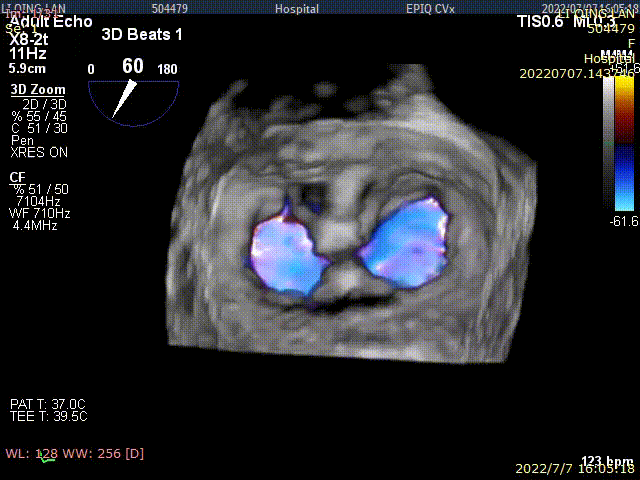

术后TEE显示,二尖瓣双孔化形成,反流明显减少